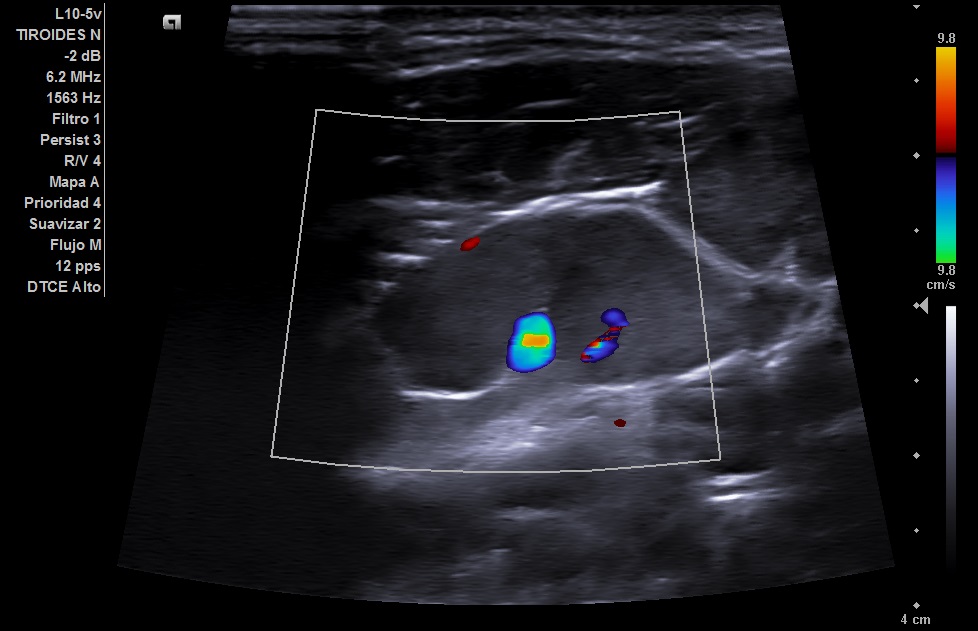

Se realizó en consulta una ecografia clínica, se colocó al paciente decúbito supino con ligera hiperextensión del cuello y tras palpar el bultoma se localizó con la sonda. Visualizamos en nivel 1 una imagen hipoecogénica ovalada de 22 mm con alteración de la estructura pero con hilio graso conservado y con aumento de vascularización compatible con adenopatía reactiva.